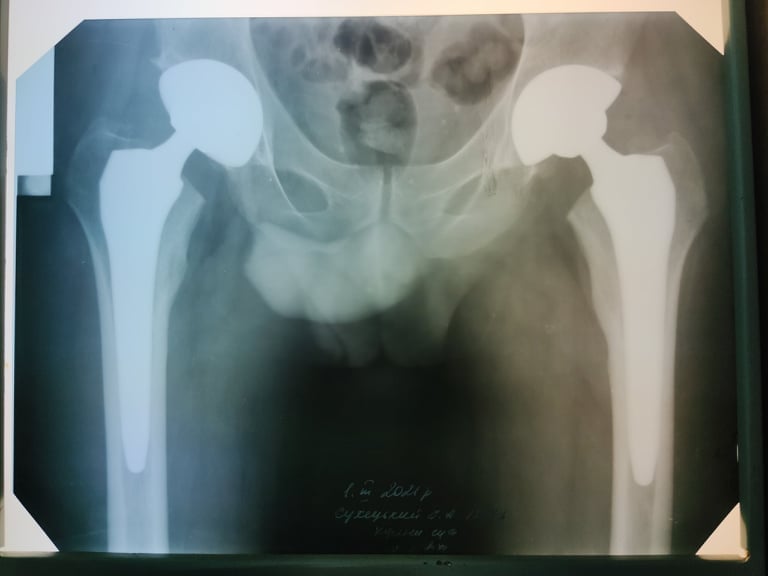

У Волинському обласному госпіталі ветеранів війни 31-річному чоловіку зробили інноваційну операцію із заміни тазостегнових суглобів, які були зруйновані асептичним некрозом. Хворому загрожувала важка інвалідність.

Операцію зробили 27 лютого, застосовуючи технологію мінідоступів, яка дає можливість уникнути травматизації м’язів, значно зменшити крововтрату та встановити ендопротези через невеликі розрізи менше 10 см.

Хірург ортопед-травматолог, завідувач хірургічного відділення госпіталю Олександр Кругляк, розповів, що своїм завданням команда лікарів бачила збереження працездатності пацієнта.«Зважаючи на молодий вік чоловіка, ми вирішили застосувати методику SuperPATH. Це мінідоступ з мінімальною травматизацією м’яких тканин. Тобто, розсікається тільки шкіра та підшкірна клітковина, а м’язи розшаровуються, і надсікається верхня частина капсули кульшового суглоба. Це, по-перше, маленький розріз (5 см), невелика крововтрата. По-друге, не травмуються м’язи і хлопець вже в перший день зміг вставати і самостійно йти. На третій день після операції об’єм рухів у нього практично такий, як у здорової людини. Він самостійно встає, ходить. Дякуємо фахівцеві відділення ортопедичної артрології та ендопротезування Інституту патології хребта і суглобів імені професора Ситенка з Харкова, який знайшов можливість приїхати та поділитися з нами своїм досвідом», - каже Олександр Кругляк.

«Асептичний некроз голівок стегнових кісток може бути однобічним, але в цього пацієнта, на жаль, двобічний. Це захворювання виникає, коли тромбуються судини, які харчують кістку і частину голівки. Поступово ця частина голівки відмирає, стає рухлива, що завдає хворому болю, і людина стає фактично інвалідом. Враховуючи молодий вік і участь в АТО, то це може бути пов’язано. Якщо взяти розгрузку, бронежилет і зброю, яку він носив, це виходить доволі значна вага. Тим більше, що її не просто треба носити, а й стрибати з БТРа, наприклад. Усе це надлишок навантаження, який може призвести до захворювання. Однак захворювання може виникнути навіть і після грипу, після гнійно-запального чи просто запального захворювання, яке призводить до згортання крові, а цей фактор може в подальшому спровокувати асептичний некроз», - зауважує Олександр Кругляк.